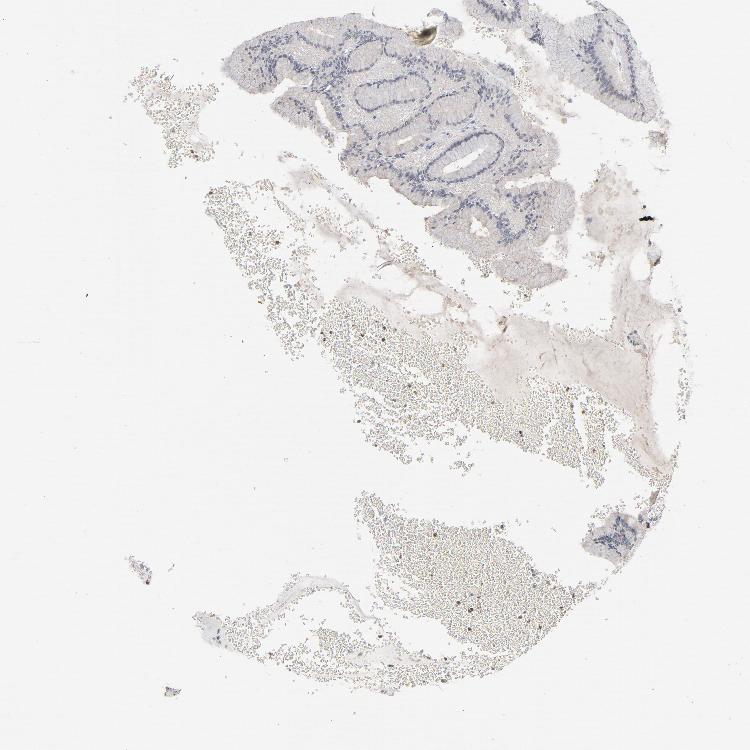

STOMACH 1 - Antibody stainingi

Antibody staining in the annotated cell types in the current human tissue is reported as not detected, low, medium, or high, based on conventional immunohistochemistry profiling in selected tissues. This score is based on the combination of the staining intensity and fraction of stained cells.

Each image is clickable and will lead to virtual microscopy that enables deeper exploration of all samples and also displays staining intensity scores, fraction scores and subcellular localization as well as patient and tissue information for each sample.

Antibody HPA003485

Glandular cells Not detected